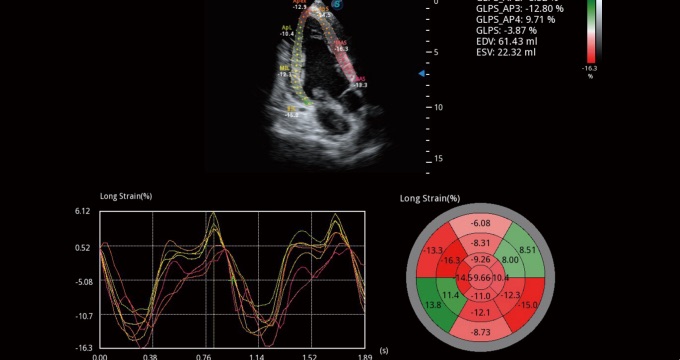

通過心肌識(shí)別技術(shù)和二維斑點(diǎn)追蹤技術(shù)相結(jié)合,計(jì)算心肌各節(jié)段的應(yīng)變應(yīng)變率、速度、位移并以曲線圖顯示,實(shí)現(xiàn)整體或者局部心肌定量分析。同時(shí)可呈現(xiàn)牛眼圖直觀和準(zhǔn)確診斷心肌的運(yùn)動(dòng)情況。